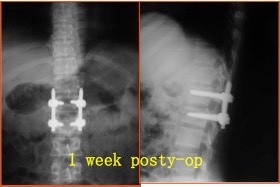

诊断:腰2椎体爆裂性骨折(AO分型:A3.1) 治疗:给予急诊行腰1-腰2椎弓根钉固定+骨折复位术。术中行椎板切除减压,用骨冲将突入椎管的骨块复位。

术后1年拆除内固定,复查骨折无明显高度丢失。